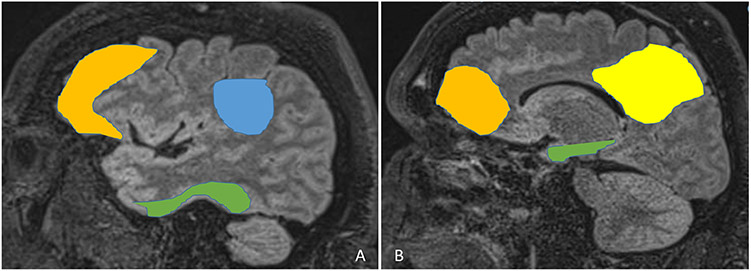

Papez circuit (Figure 2) connects hippocampus via fornix to mammillary body and anterior nucleus of thalamus which sends projections via cingulate gyrus to parahippocampal gyrus which connects back to the hippocampus, and plays a major role in memory consolidation23. Various degrees of alteration in the papez circuit is observed in AD. Similarly, alteration of the papez circuit is often implicated in many PwE especially those with MTLE, and various regions of the papez circuit are increasingly being studied and used as therapeutic targets for neuro-modulation in the management of drug-resistant epilepsy23.

Figure 2: Papez Circuit:

The memory pathway and the pathway for seizures are the same. The interaction between different structures is demonstrated. A: Shows a simplified version of the Papez circuit, while B demonstrates the structures on a sagittal MRI scan. ATN: Anterior thalamic nucleus.